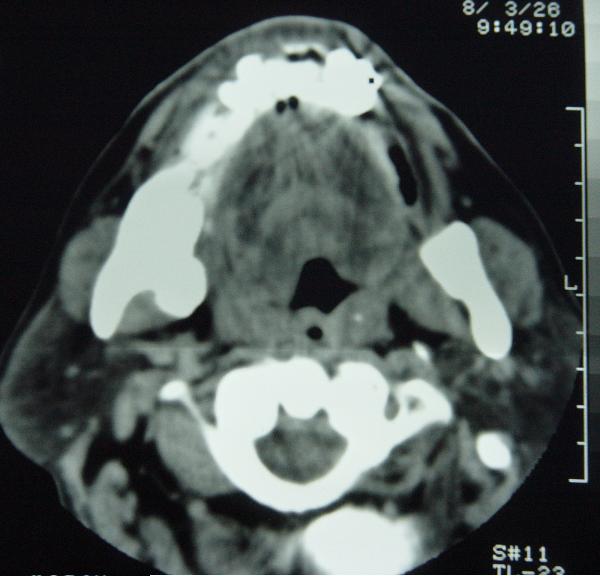

标题: CT12465:下颌骨肿瘤,请会诊 [打印本页]

标题: CT12465:下颌骨肿瘤,请会诊

发现下颌骨肿瘤近30年.逐渐增大.

考虑右侧下颌骨水平部及升部骨纤维异常增殖症可能性大。

考虑右侧下颌骨骨化性纤维瘤。